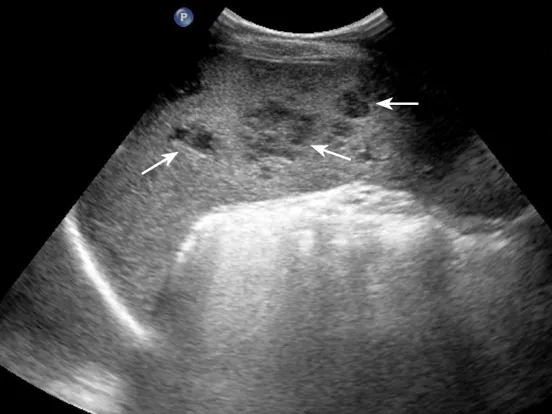

灰阶超声显示脾内多个低回声团块,呈分叶状,形态不规则(箭头所示)。